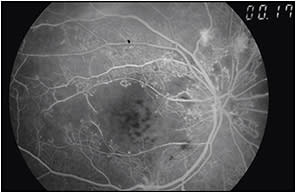

Ordering FFA at the first visit is mandatory in cases of featureless retina with very poor BCVA to exclude ischemic DME because these patients have poor prognoses and will not benefit from any treatment in which OCT cannot detect ischemic diabetic maculopathy4 but may show evidence of ganglion cell layer damage.5

Perfusion status. The perfusion status of the macula and retinal periphery with ischemia (Figures 13 and 14) indicates a poor prognosis with no beneficial treatment. Such cases can present as a large foveal avascular zone (FAZ) or a FAZ with irregular borders.

Figure 13. Fundus photo of featureless retina with signs of macular ischemia. BCVA was counting figures.

Figure 14. Fundus FA of the patient in Figures 12 and 13 shows a large FAZ and capillary dropout.